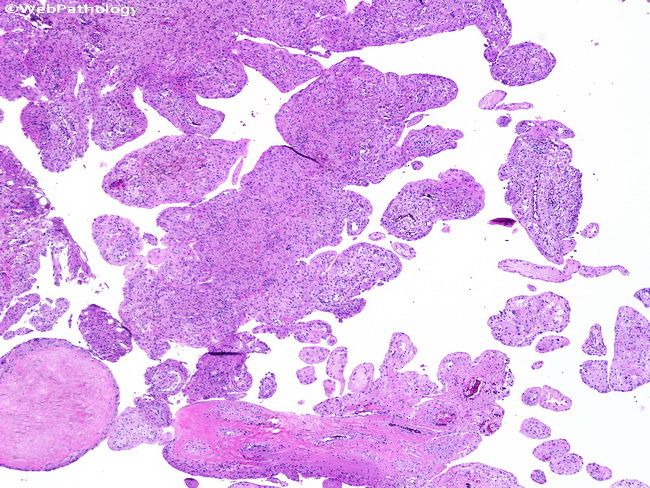

Пигментный виллонодулярный

Пигментный виллонодулярный 113 фотографий